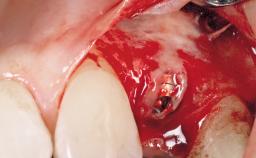

Late Placement of an Implant in a Maxillary Left Central Incisor Site

Bone Augmentation Horizontal|Staged

Augmentation Materials Xenogenous|Membrane

Soft Tissue Grafting Simultaneous

Bone Volume Deficient horizontally, requiring prior grafting